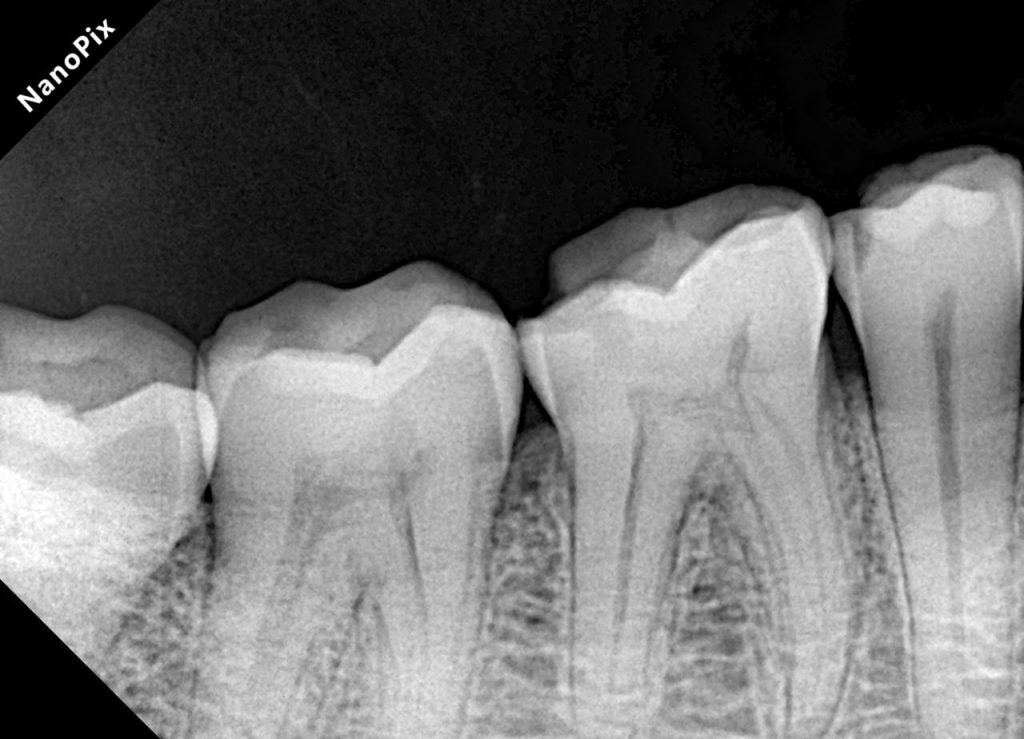

Radiographs (Pre-op)

Image 1–2:

“Pre-operative bitewing radiographs showing proximal caries in posterior trio, with preserved pulp vitality and no signs of apical pathology.”